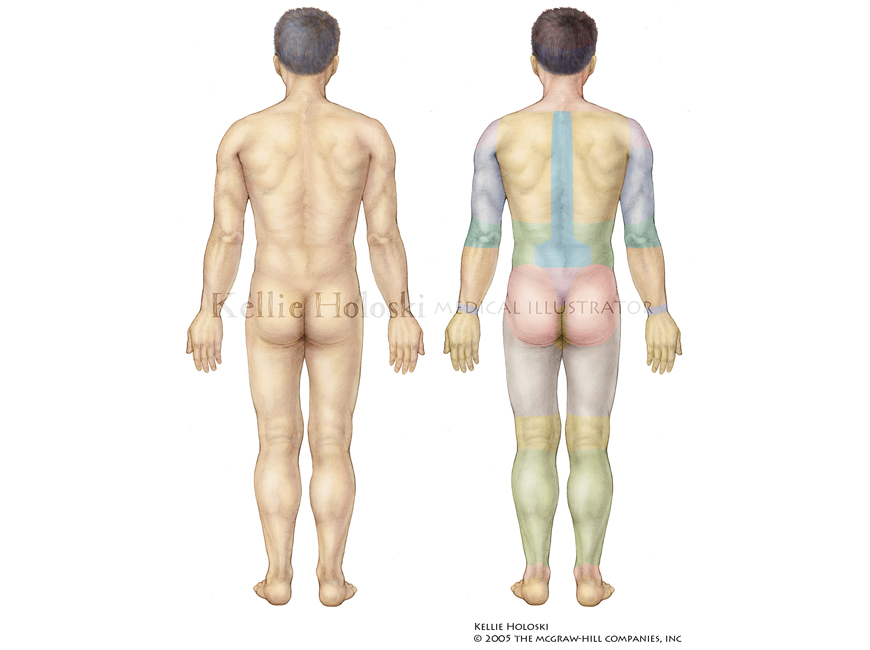

Dermatomes,

Graphite and Adobe Photoshop

Published in Human Anatomy, 1st Edition by Michael McKinley, Valerie O’Loughlin;

©The McGraw-Hill Companies -